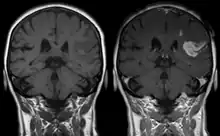

Gadolinium(III) containing MRI contrast agents (often termed simply "gado" or "gad") are the most commonly used for enhancement of vessels in MR angiography or for brain tumor enhancement associated with the degradation of the blood–brain barrier (BBB).[3][4] Over 450 million doses have been administered worldwide from 1988 to 2017.[5] For large vessels such as the aorta and its branches, the dose can be as low as 0.1 mmol/kg of body mass. Higher concentrations are often used for finer vasculature.[6] At much higher concentration, there is more T2 shortening effect of gadolinium, causing gadolinium brightness to be less than surrounding body tissues.[7] However at such concentration, it will cause greater toxicity to bodily tissues.[8]

Gd3+ chelates are hydrophilic and do not readily cross the intact blood–brain barrier. Thus, they are useful in enhancing lesions and tumors where the blood–brain barrier is compromised and the Gd(III) leaks out.[9][a] In the rest of the body, the Gd3+ initially remains in the circulation but then distributes into the interstitial space or is eliminated by the kidneys.